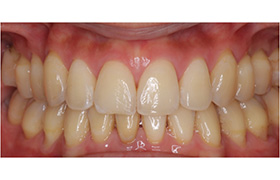

Before

After

歯牙移植(骨の移植)

むし歯や歯周病で歯を失った後に、通常必要のない親知らずを、なくなった箇所に移植することによって健康な歯並びを回復する事ができます。

※移植には適合のための条件があります。